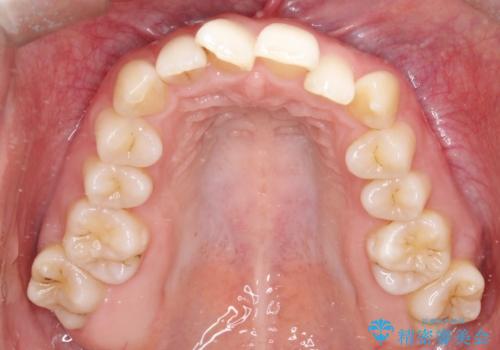

- 患者様は、前歯のガタガタ(叢生)と左下5番の欠損部が気になるとのことで来院されました。診断の結果、インビザラインを用いて前歯の叢生を整えながら、左下5番の欠損部にはインプラント治療を計画しました。矯正治療により、歯並びを改善すると同時に、噛み合わせのバランスも向上させることを目標としました。矯正期間とインプラントの治療計画を並行して進めることで、患者様のご希望に応えるプランを立てました。

前歯の叢生改善のため、インビザラインによる透明で目立たない矯正装置を使用しました。治療中は、歯の移動による負担を最小限に抑えつつ、歯列全体のバランスを考慮して進めました。左下5番の欠損部には、矯正終了後にインプラントを埋入し、自然で機能的な咬合を回復しました。治療期間中、患者様には装置の正しい装着と日々の清掃を徹底していただき、歯肉やインプラント周囲の健康を保つようサポートしました。結果として、美しい歯並びと快適な噛み合わせを両立させることができました。